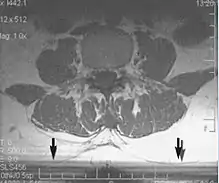

Slice-to-slice interference

Non-uniform RF energy received by adjacent slices during a multi-slice acquisition is due to cross-excitation of adjacent slices with contrast loss in reconstructed images (Fig. 11). To overcome these interference artifacts, the acquisition of two independent sets of gapped multi-slice images need to be included, and subsequently reordered during display of the full image set.[1]